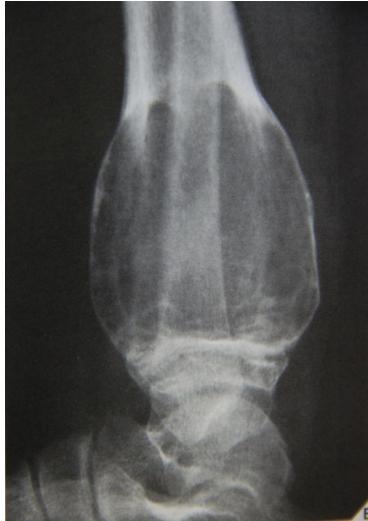

Aneurysmal Bone Cyst

site: Distal tibial

size:  Involving most of distal part

matrix: Cortical expansion, radiolucent matrix, well defined, narrow zone of transition

soft tissue involvement:  no peristeal reaction